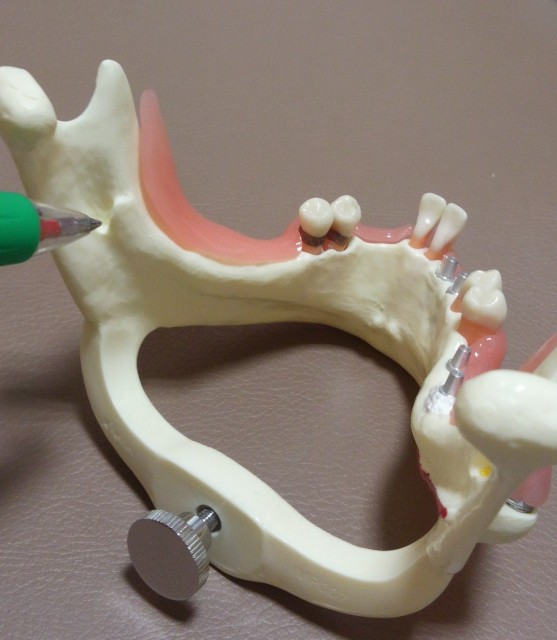

美容室MのA君の歯牙腫はカイン。

カインの傍らには殺された弟のアベルが横たわっていました。

アベル恨みは根深く、悪いものになってしまいました。

アベルの血は地中深く滲みわたり、

含歯性嚢胞(がんしせいのうほう)になっています。

さあ手術です。

カインをエデンの東にあるノドの地へ追放した後、アベルを葬送しなくてはなりません。